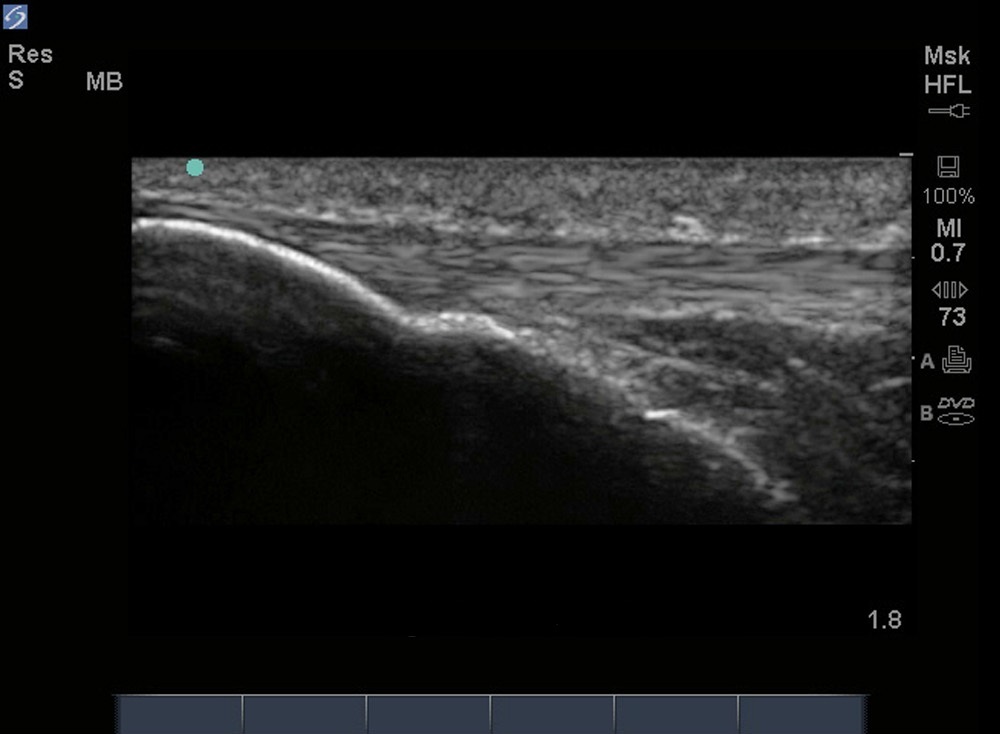

Genou - Image - Tendon patellaire sagittal